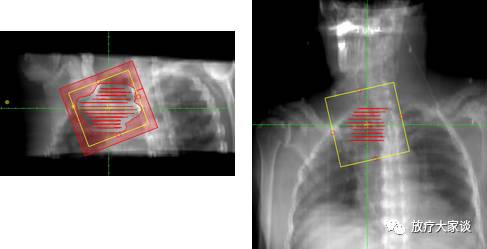

4.4 BEV

DRR

放疗计划系统有哪些放射治疗计划系统(TPS)介绍_https://www.jmylbn.com_新闻资讯_第6张